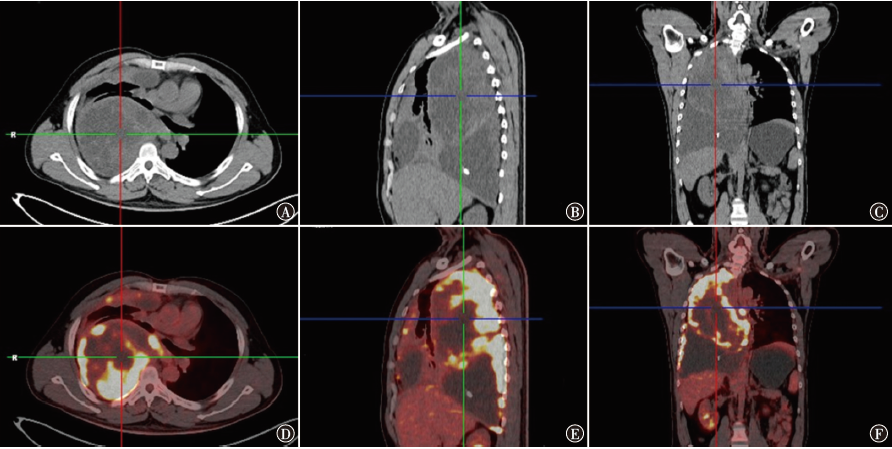

尤文肉瘤/原始神经外胚层瘤是一种神经外胚层分化的小圆细胞恶性肿瘤。现报道1例肺原发尤文肉瘤/原始神经外胚层瘤患者的诊疗情况,复习相关文献并进行讨论,以提高对该类疾病的认识。